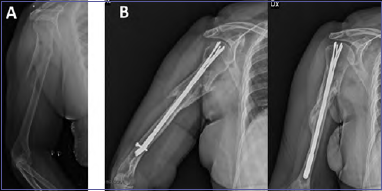

Hongjie Wen et al. in 2019 performed a meta-analysis to compare the efficacy and safety between antegrade IMN and plating for humeral shaft fracture, concluding that IMN may be superior to open reduction and internal fixation (ORIF) in reducing blood loss and post-operative infections, but inferior to minimally invasive plate osteosynthesis (MIPO) in nonunion rate. In the same study they found no statistically significant differences in operation time, functional results (evaluated with American Shoulder and Elbow Surgeons (ASES) score), rate of nerve injury, delayed union and need for reoperation 27 (Figs. 5A, B; Figs. 6A, B, C, D, E, F).

Figure 5.Clinical Case 5. AO 12A3 female 44y. Anterograde intramedullary nail osteosynthesis with good reduction and healing of the fracture site. A) pre-operative X-ray; B) X-ray after 17 months after trauma show radiological healing.

Figure 6.Clinical Case 6. AO 12B3 male 34y polytrauma. Intramedullary nail fixation without compression on fracture side led to nonunion. A) pre-operative X-ray; B) X-ray post-operative treatment; C) X-ray 1 year after trauma show nonunion; D) revision with compression plate and opposite bone graft; E) X-ray 1 year after revision show radiological healing of the nonunion; F) clinical photos 6 months after revision surgery show very good functional recovery.